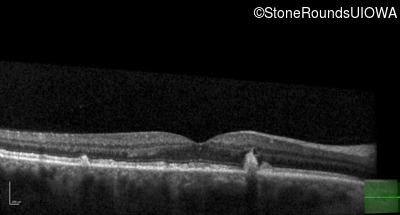

Pattern Dystrophy (IIC)

Age at visit: 49 years

This 49 year old man was first told he had a fundus abnormality on a routine eye exam at age 34. Ten years later he noticed some distortion just superior to fixation.

Pattern Dystrophy PRPH2 Gln239Stop CAG>TAG   AD